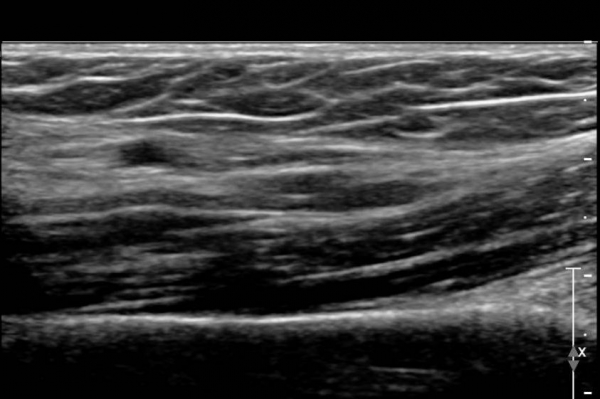

ŽÃËÀÚ¸¦ »ó¹ÚºÎ ¸»´ÜÀ¸·Î  ¿Å°Ü ÆÈ²ÞÄ¡ ºÎÅÍ ±ÙÀ§ºÎ·Î À̵¿ Çϸ鼭 Á¤Á߽Űæ Ⱦ´Ü¸é°Ë»ç¸¦

½ÃÇàÇÏ¿´´Ù(»çÁø 2).  ÆÈ²ÞÄ¡ ÁÖ¸§  ¾à  3cm ±ÙÀ§ºÎ¿¡¼­ Á¤Á߽ŰæÀÇ ÀϺΠ´Ù¹ß(fascicle)ÀÇ Àú¿¡ÄÚ ºÎÁ¾ÀÌ

°üÂûµÈ´Ù(»çÁø 3 , 4,  5,).